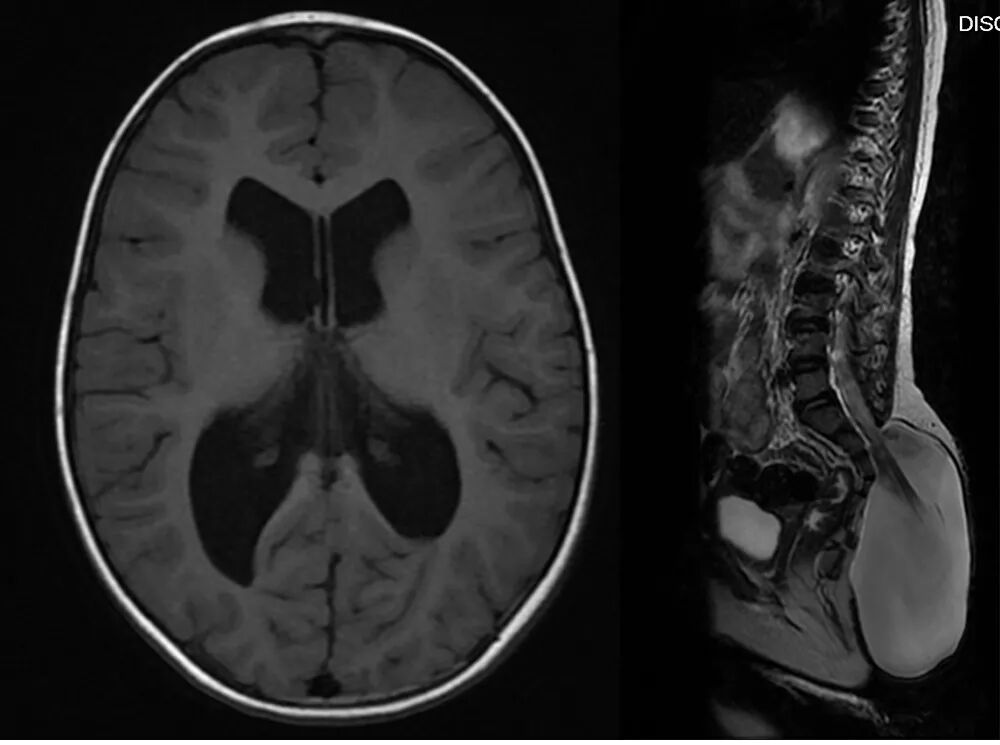

MR扫描显示骶尾段脊髓脊膜膨出,脑积水,Chiari畸形II型。

术前诊断:骶尾段脊柱裂(脊髓脊膜膨出),Chiari畸形II型,脑积水,双侧神经源性马蹄内翻足。